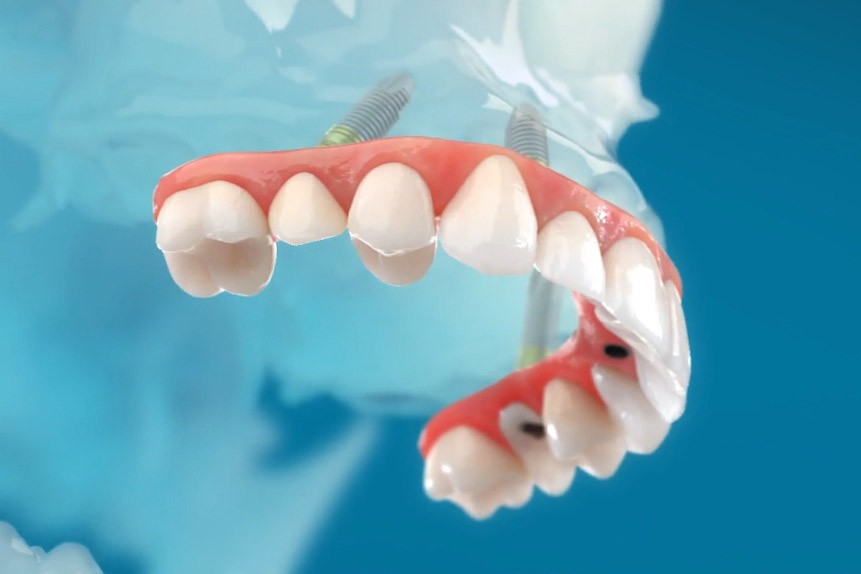

Mosty montowane na stałe na implantach

Istnieje cały szereg koncepcji, które przy użyciu implantów rozwiązują problem rehabilitacji implantoprotetycznej bezzębia. Rodzaj zastosowanej procedury, wynikająca z niej ilość użytych implantów uzależnione są przede wszystkim od:

Technologia konstrukcji mostów protetycznych uzależniona jest z kolei od ilości i rodzaju implantów użytych jako fundamentu dla planowanych uzupełnień protetycznych.

- Rozwiązania protetyczne w systemie all-on-4 uwzględniają możliwość wykonania stałych prac protetycznych, czyli mostów zamocowanych na stałe, jak również protez ruchomych wspartych jedynie na implantach.

Przy bezzębiu zawsze istnieje możliwość wykonania uzupełnień protetycznych bez zastosowania implantów i są to całkowite protezy osiadające. W zależności od stanu kości szczęk i żuchwy można wykonać protezy lub mosty mocowane na implantach. Mocowanie protez na implantach może być rozłączne, jak w przypadku protez Overdenture, zwanych również nakładowymi. Oznacza to, że proteza w każdej chwili może być odczepiona od platform implantów przez pacjenta i wyjęta z jamy ustnej. Najbardziej jednak pożądane przez pacjentów rozwiązania protetyczne przy bezzębiu to stabilne, niezdejmowalne mosty, które cementuje się lub przykręca na stałe do implantów. One najlepiej imitują estetykę i funkcję naturalnego uzębienia.